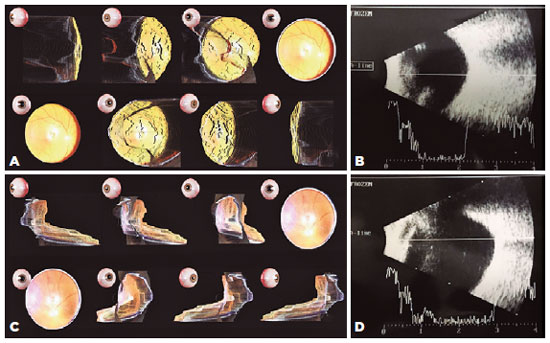

After obtaining ethical approval for the study, we tested the portable device on a myopic eye (11 diopters) and on an emmetropic eye. To capture the pictures, the eyes were dilated with 1% tropicamide, and FocosTM by Xiaodong Wang (created in 2017) was configured with the following perks: continuous shooting mode, export size of 1536 × 2048 and flashlight set to torch. After image capture, we used the FocosTM application’s “effect” perk to process the images (Figure 2).

We were able to acquire 3D fundus images by using our smartphone model. In analyzing the pictures, the four general ophthalmologists and the retina specialist were able to identify a staphyloma on the myopic eye, but only the retina specialist was able to locate the staphyloma with ocular echography. The echography performed by the five ophthalmologists’ revealed similar axial lengths in each eye: 29.5 mm in the myopic eye and 22.3 mm in the emmetropic eye (Figure 2).

Despite some glare and artifacts common on pictures of the fundus taken by smartphones(1), our 3D images have good reliability. In analyzing the optic nerve in the image of the myopic eye, we were able to verify that it was located superiorly within the staphyloma, as which corresponded to the findings on echography (Figure 2).